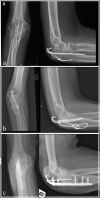

Tension band wiring for simple olecranon fractures: a) Pre-operative radiographs b) Post operative radiographs showing parallel K-wires engaging the volar cortex.

Complications of olecranon fixation: a) Longer wires penetrating the volar cortex risk injuring the posterior interosseus nerve b) shorter wires that do not engage the volar cortex increase the risk of backing out of the wires c) Inadequate capture of the proximal fragment and subsequent failure.